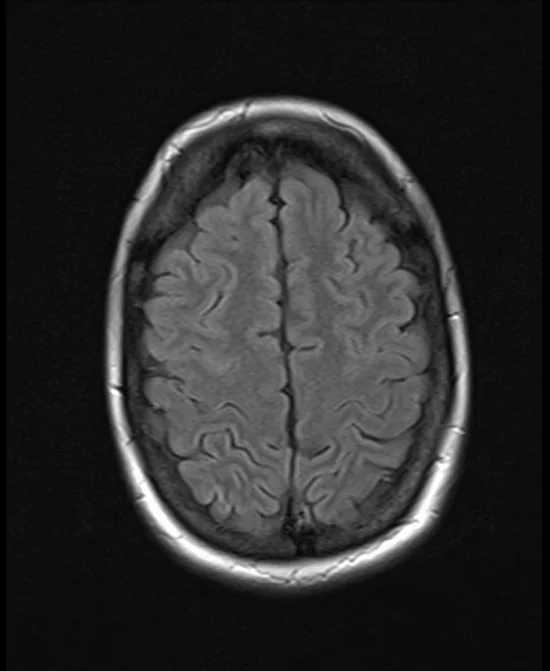

brain mri t2 flair axial images